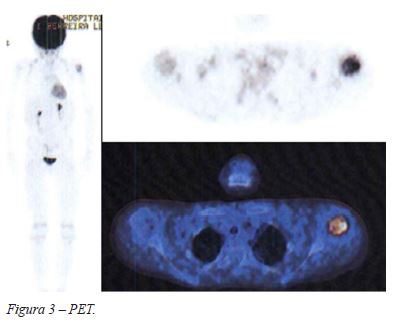

Ao exame objetivo apresentava dor à palpação do úmero proximal e ombro esquerdo e limitação da abdução ativa a partir dos 30°. A radiografia do ombro revelou uma lesão permeativa da metáfise umeral proximal, com bordos mal definidos e erosão da cortical medial (Figura 1). Na ressonância magnética (RMN) a lesão apresentava hipossinal em T1 e hipersinal em T2, medindo aproximadamente 6,2cm de maior extensão. Não havia evidência de atingimento da fise de crescimento, embora se observasse pequeno foco de hipersinal na vertente antero-medial da epífise. No terço médio da diáfise umeral existia uma área nodular, com 7mm de maior eixo, com hipossinal em T1 e hipersinal em T2, suspeita de corresponder a skip lesion (Figura 2). A tomografia por emissão de positrões revelou uma hipercaptação anómala de fluorodesoxiglucose a nível do úmero proximal e 3 micronódulos pulmonares bilaterais milimétricos (Figura 3).